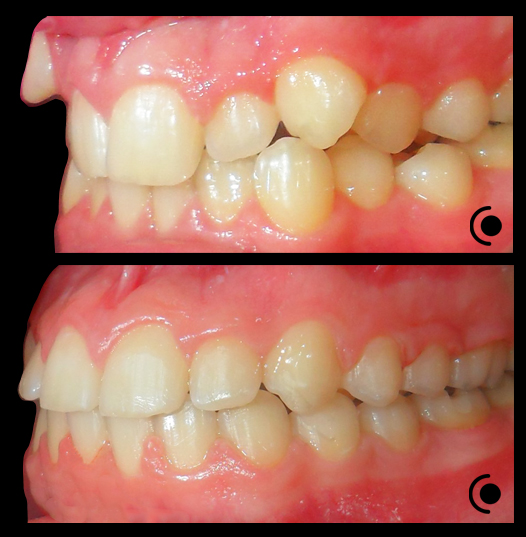

O našoj kvaliteti najbolje govore naši rezultati!

Centar za ortodonciju Petra Džapo